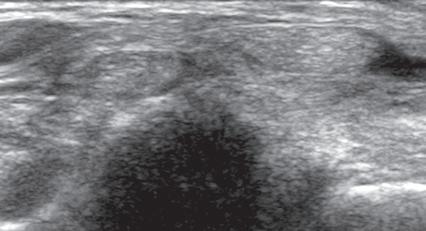

One should be familiar with several artifacts common to musculoskeletal ultrasound.5 One

such artifact is anisotropy 6 When a tendon is imaged perpendicular to the ultrasound beam, the characteristic hyperechoic fibrillar appearance is displayed. However, when the ultrasound beam is angled as little as 2 to 3 degrees relative to the long axis of such a structure, the normal hyperechoic appearance is lost; the tendon becomes more hypoechoic with increased insonation angle (Figs. 1.10 to 1.13). A tissue is anisotropic if its properties change when measured from different directions. This variation of ultrasound interaction with fibrillar tissues involves tendons and ligaments and, to a lesser extent, muscle. Because abnormal tendons and ligaments may also appear hypoechoic, it is important to focus on that segment of tendon or ligament that is perpendicular to the ultrasound beam, to exclude anisotropy. With a curved structure, such as the distal aspect of the supraspinatus tendon, the transducer is continually repositioned or angled to exclude anisotropy as the cause of a hypoechoic tendon segment (Fig. 1.11 and Video 1.3). Anisotropy is noted both in long axis and short axis of ligaments and tendons (Video 1.4), but it occurs when the sound beam is angled relative to the long axis of a structure (Fig. 1.12). Therefore, to correct for anisotropy, the transducer is angled along the long axis of the imaged tendon or ligament; when imaging a tendon in long axis, the transducer is angled as a heel-toe maneuver (see Fig. 1.3A and Video 1.5), whereas in short axis, the transducer is toggled (see Fig. 1.3B and Video 1.6). Anisotropy can be used to one’s advantage in identification of a hyperechoic tendon or ligament in close proximity to hyperechoic soft tissues, such as

FIGURE 1.10 Anisotropy. Ultrasound image of flexor tendons of the finger in long axis shows normal tendon hyperechogenicity (arrowheads) becoming more hypoechoic as the tendon becomes oblique relative to the sound beam (open arrows). P, Proximal phalanx.